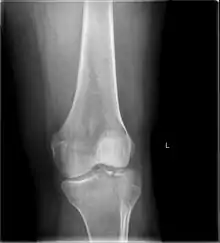

![]() | |

| A severe tibial plateau fracture with an associated fibular head fracture | |